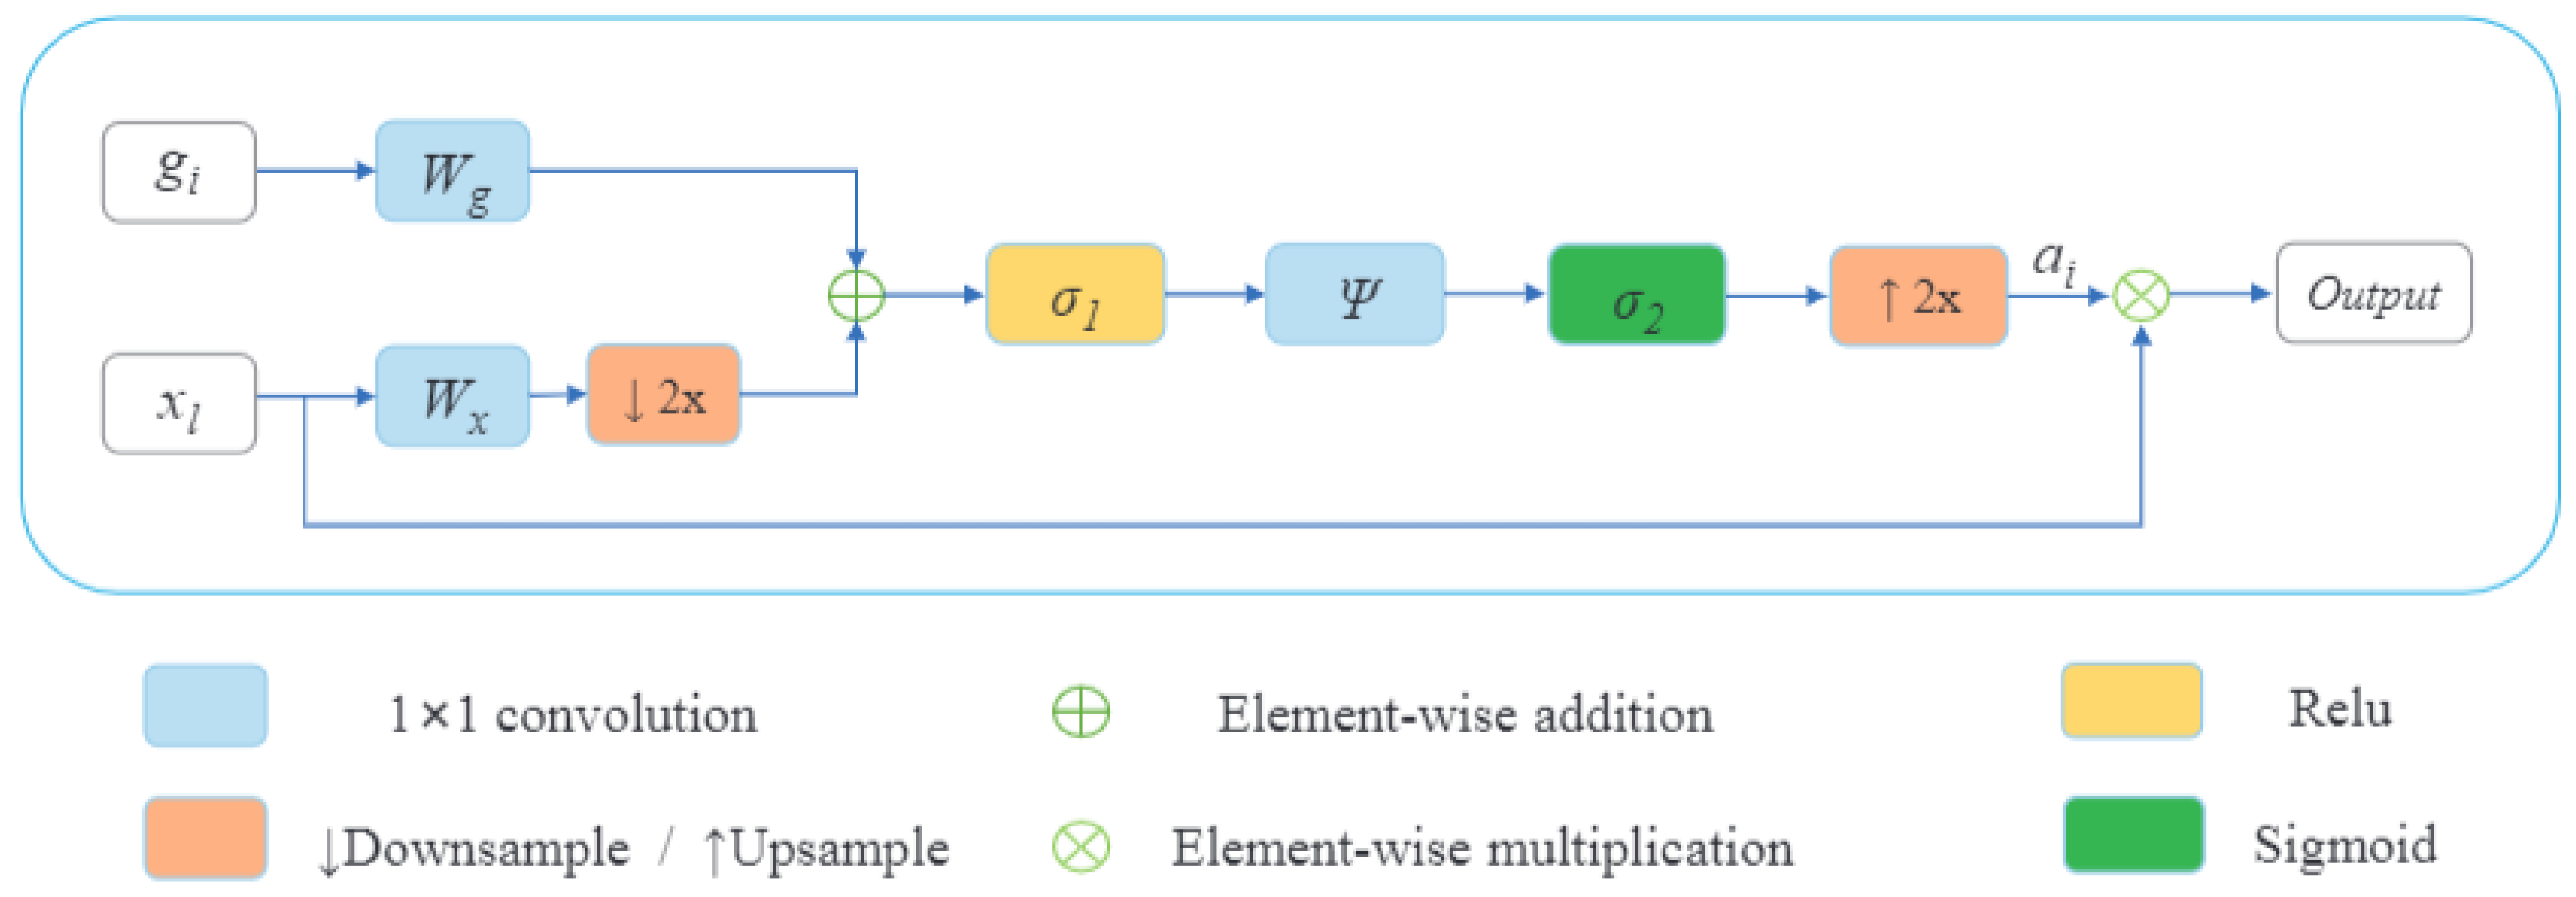

2.2.2. Decoder